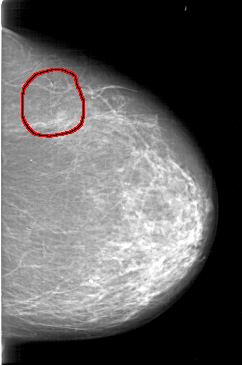

D_4198_1.RIGHT_MLO

LEFT_MLO LINES 5476 PIXELS_PER_LINE 4351 BITS_PER_PIXEL 12 RESOLUTION 43.5 OVERLAY

FILE: D_4198_1.LEFT_MLO.OVERLAY

TOTAL_ABNORMALITIES 1

ABNORMALITY 1

LESION_TYPE CALCIFICATION TYPE ROUND_AND_REGULAR-PLEOMORPHIC DISTRIBUTION CLUSTERED

ASSESSMENT 0

SUBTLETY 4

PATHOLOGY BENIGN

TOTAL_OUTLINES 1

BOUNDARY